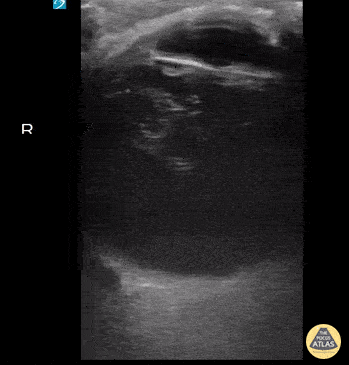

UPLOADS FOR REVIEW - Viterous Hemorrhage

76 year old male with a PMH of malignant ocular melanoma and blindness of the right eye presented due to right sided headache for the last 2 days. Michael Bernard, DO; Thomas Taugher, DO; Marko Lubardic; Central Michigan University Residency in Emergency Medicine